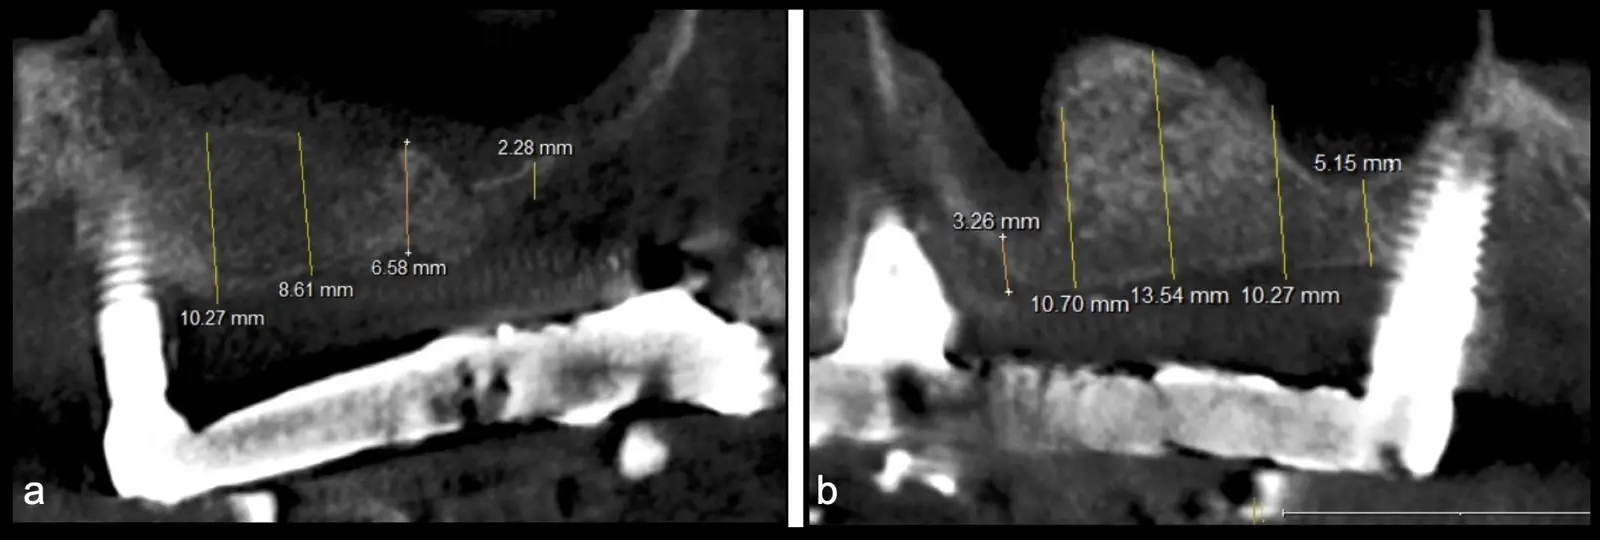

El levantamiento de piso de seno maxilar es una técnica quirúrgica aceptada previa o simultáneamente a la colocación de implantes dentales. La mayor evidencia científica refiere que si se tiene entre 0 -7 mm de altura ósea se debe realizar la elevación sinusal junto con injertos óseos; y a partir de los 8 mm, se hace más predecible la colocación simultánea de implantes dentales.1-3

El tipo de inserto a ser utilizado dependerá del espesor de la pared ósea. Si la pared es menor a 0.5 mm, es mejor utilizar insertos de desgaste para prevenir la ruptura de la membrana de Schneider; si el espesor es mayor a 0.5 mm, se puede utilizar insertos de corte de espesor medio (Figura 3).

El clínico puede retirar la tabla ósea o introducirla como “tienda de campaña” dentro del seno maxilar. En cualquiera de las alternativas, es importante evaluar la presencia de tabiques óseos y de la arteria postero alveolar superior.